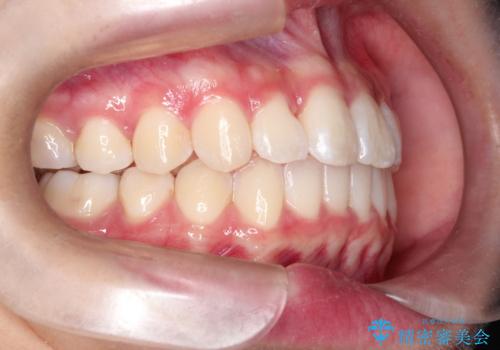

前歯のがたがたを綺麗にしたい

- 前歯がねじれていること、出ていることを主訴に来院されました。

前歯の突出感も改善され、満足していただきました。